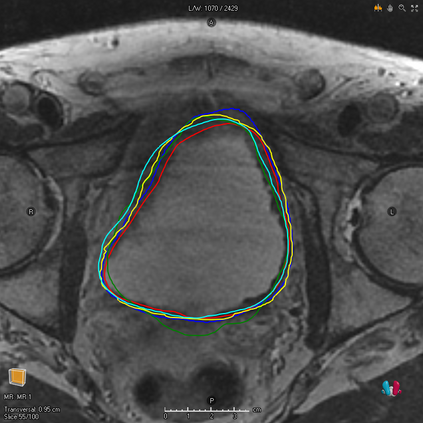

We study two of the most popular performance metrics in medical image segmentation, Accuracy and Dice, when the target labels are noisy. For both metrics, several statements related to characterization and volume properties of the set of optimal segmentations are proved, and associated experiments are provided. Our main insights are: (i) the volume of the solutions to both metrics may deviate significantly from the expected volume of the target, (ii) the volume of a solution to Accuracy is always less than or equal to the volume of a solution to Dice and (iii) the optimal solutions to both of these metrics coincide when the set of feasible segmentations is constrained to the set of segmentations with the volume equal to the expected volume of the target.